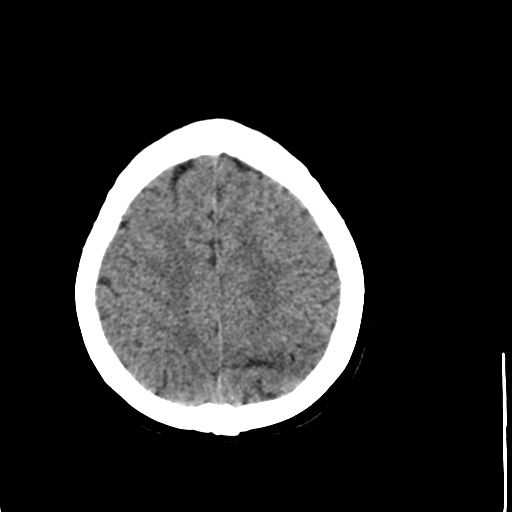

病人资料:女,57岁,反复头痛6年余,无恶心、呕吐等症状,体查:bp180/100mmhg。

脂肪瘤

脂肪瘤。

颅内脂肪瘤

中线脂肪瘤

中线脂肪瘤,支持

胼胝体发育不良并脂肪瘤形成,脂肪瘤形成是因,胼胝体发育不良是果。如果正规些应该是中线脂肪瘤并胼胝体发育不良!

典型中线脂肪瘤

胼胝体发育不良

中线脂肪瘤并胼胝体发育不良。